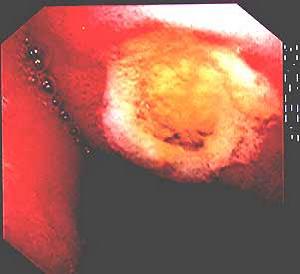

2.胃鏡檢查:陽性率可達80%~95%,在診斷上消化道出血方面比X 線胃腸鋇劑造影優越。胃鏡檢查不僅能看見病變的性質,而且可以看到活動或近期出血的可靠徵象,即新鮮出血或滲血,病變區呈黑褐色底或附有凝血塊。根據北京8個大醫院施行急診胃鏡檢查248 例的經驗總結,認為並不增加大出血的危險。必要時,可在內鏡下進行止血治療。只要病人的血壓穩定接近正常,消除病人的顧慮與緊張後,就在病床旁或手術台上進行。檢查過程應輕巧、迅速。避免粗暴插鏡動作。檢查的時間應在出血後24~48h 內進行。否則一些淺表性黏膜病變如糜爛、淺潰瘍、黏膜撕裂等,可由於部分或全部修復而失去診斷徵象。檢查前並不需要洗胃,若因積血影響觀察,可於檢查前經胃管用冰水洗胃。觀察應該全面,不要滿足於發現一處病變即作結論。需對食管、胃、十二指腸細緻察看以後,再作出診斷,必要時可取活體做病理檢查,但須警惕胃底部的靜脈曲張有時呈灰色結節狀隆起,然觸之柔軟有彈性,輕易取活檢有引起嚴重出血危險。